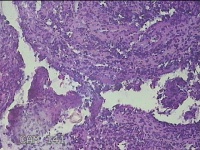

右侧卵巢囊肿

性别

女

年龄

36岁

临床诊断

一般病史

发现双侧附件囊肿1年。

标本名称

大体所见

灰白暗红色囊壁样组织2.5x2x0.3cm一块,表面光滑,部分已切开,囊内容物已流失,囊壁厚0.2cm。

考虑:子宫内膜异位囊肿。